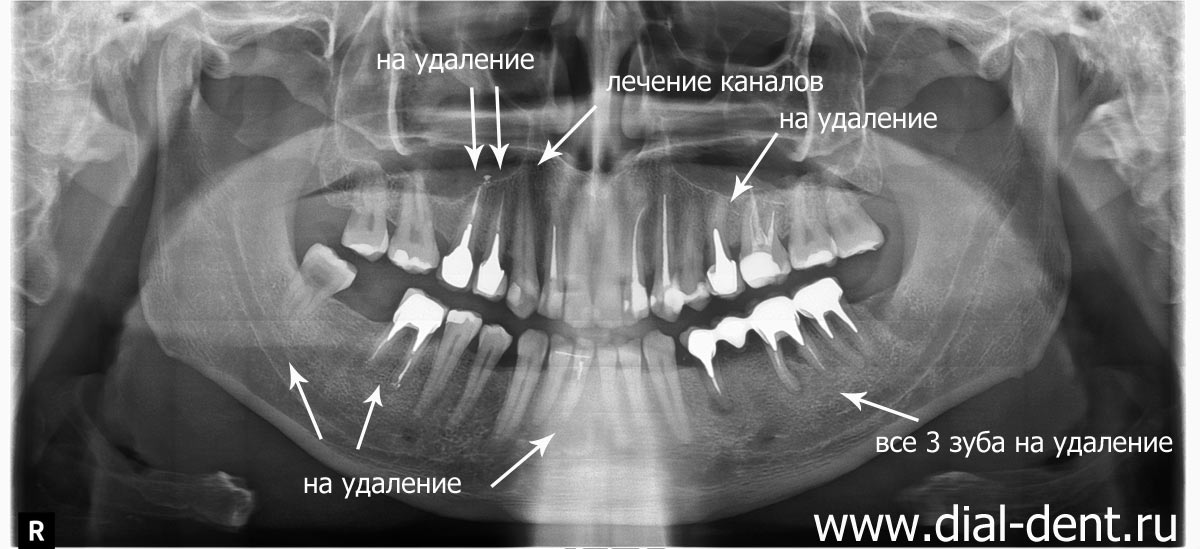

Дентальные снимки и диагностика кариеса